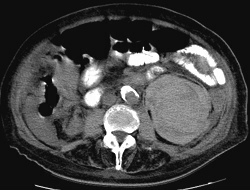

RADIOLOGY: KIDNEY: Case# 32991: RENAL MASS C PERINEPHRIC HEMATOMA. This is a 91 year old female with a history of congestive heart failure with a pace maker. She also has a history of constipation, nausea and vomiting. She has heme positive stools plus increased WBC count. This CT is performed to rule out bowel obstruction. A large heterogeneous mass is seen in the left kidney with a very large collection of high attenuation fluid(hematoma) in the subcapsular space. This is consistent with renal cell carcinoma which has bled, creating hematoma in the left subcapsular space. This kidney and entire subcapsular space are now 4 to 5 times the size of the right kidney. No signs of bowel obstruction are seen. Pace maker wires are seen along with cardiomegaly. There are bilateral pleural effusions with atelectasis. Degenerative changes are noted to the vertebra, along with atherosclerotic calcific changes to the aorta, iliacs and femoral arteries. Perihepatic and perisplenic fluid is seen. The liver is normal in shape . No intrahepatic lesions are seen. The hepatic veins are prominent consistent with high central venous pressure. The adrenal glands and the right kidney are normal. The pancreas is not well seen. Free fluid is also seen in the right pericolic gutter.